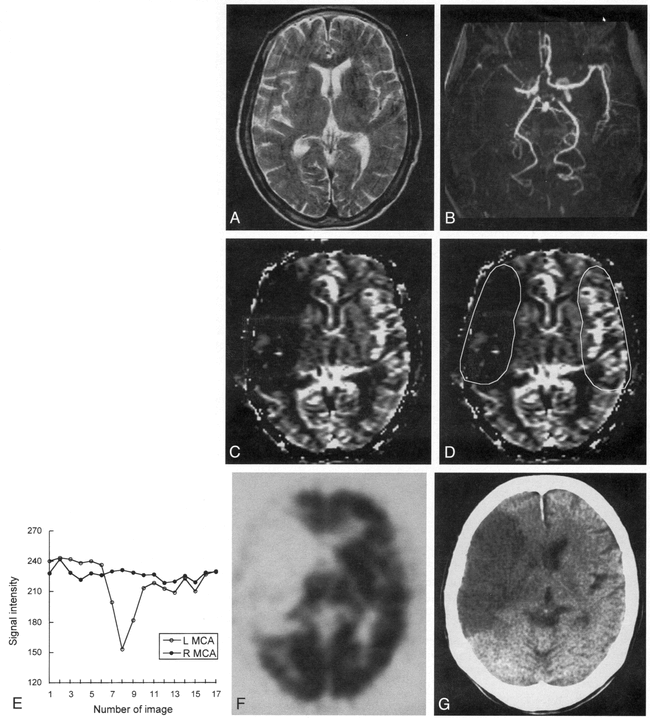

Case 8: 77-year-old woman with hyperacute ischemic stroke with arterial occlusion and decreased CBV.

A, T2-weighted MR image (3500/90) is normal except for abnormal subtle high signal intensity in right basal ganglia.

B, 3D time-of-flight MR angiogram reveals occlusion at M1 segment of the right MCA.

C, CBV map shows decreased CBV in right MCA distribution.

D, CBV map shows irregular ROIs placed for measurement of CBV ratio and time–signal intensity curves between the region of decreased CBV and contralateral normal region. Calculated CBV ratio was 0.17.

E, Time–signal intensity curves measured during passage of contrast material show no signal change in right MCA distribution compared with normal signal reduction in left MCA distribution.

F, 99mTc-HMPAO brain SPECT scan obtained during the hyperacute stage at approximately the same level as A and C reveals severe hypoperfusion throughout right MCA distribution.

G, Follow-up CT scan 3 days after the onset of symptoms shows well-defined infarction in right MCA distribution, which corresponds to the region of decreased CBV.

Time–signal intensity curves showed no reduction of signal intensity in the region of decreased CBV in any of the eight patients with the pattern of arterial occlusion and decreased CBV (Fig 1E). In two patients with the pattern of arterial occlusion and increased CBV, delayed arrival time and delayed washout of the contrast material in the region of increased CBV was observed, suggesting recruitment of blood flow through collaterals (Fig 2E). In two patients with the pattern of no arterial occlusion and normal CBV, there were no differences in signal reduction, arrival time, or washout pattern of the contrast material between the hemispheres.

Brain SPECT was performed in nine of 12 patients. The mean CBF ratios measured on SPECT were 0.39 (range, 0.20–0.65) in six patients with the pattern of arterial occlusion and decreased CBV (Fig 1F), 0.85 (range, 0.81–0.89) in two patients with the pattern of arterial occlusion and increased CBV (Fig 2F), and 0.99 in one patient with the pattern of no arterial occlusion and normal CBV. Although CBF ratios in these three imaging patterns were obviously different, there was no statistically significant difference, owing to the small number of patients (P = .061 by Kruskal-Wallis test).

Follow-up CT or MR examinations in all eight patients with the pattern of arterial occlusion and decreased CBV showed infarctions, whose extent correlated well with the region of CBV and CBF abnormalities (Fig 1G). In two patients with the pattern of arterial occlusion and increased CBV, infarctions did not develop on initial follow-up images (Fig 2G). The development of infarctions was statistically significantly different between these two patterns (P = .022 by Fisher's exact test). In one patient (case 9), however, watershed infarction developed in the cerebral deep white matter 3 days after the first follow-up study. In two patients with the pattern of no arterial occlusion and normal CBV, follow-up imaging was not performed.